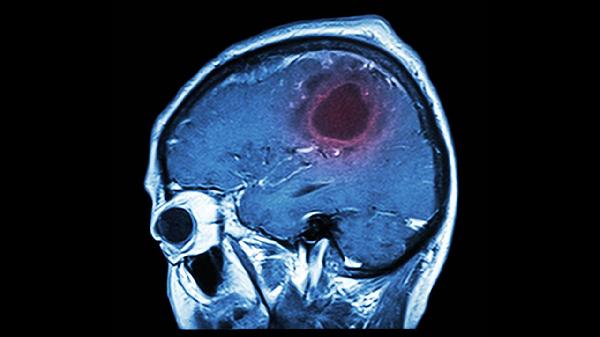

人不会无缘无故患上脑溢血,研究发现:脑溢血患者多半爱干这3事

凌晨三点刷手机的夜猫子们注意了,你们手里发亮的屏幕可能正在悄悄改写脑血管的命运。那些总说"猝死离我很远"的年轻人,现在连ICU的医生都开始用"青年卒中"这个新词了。